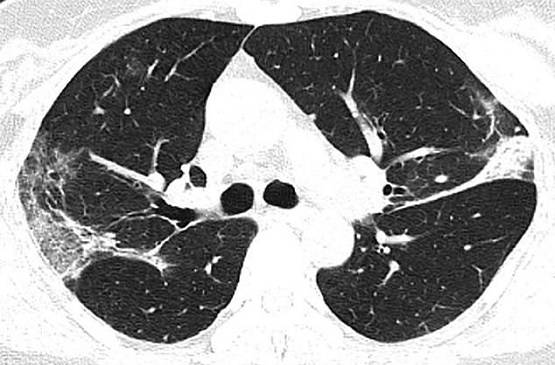

चीन में एक 44 वर्षीय महिला की मौत कोरोना वायरस की वजह से हुई थी. महिला की मौत के बाद जब उसके शरीर का एक्स-रे और सीटी स्कैन किया गया तो दिल दहला देने वाली तस्वीरें सामने आईं.

महिला के शरीर की स्कैन रिपोर्ट रेडियोलॉजिस्ट सोसायटी ऑफ नॉर्थ अमेरिका ने जारी की है. तस्वीरें देखकर ये साफ अंदाजा लगाया जा सकता है कि कोरोना वायरस इंसान के फेफड़ों को कैसे खराब करता है.

फेफड़ों में नीचे की तरफ कॉर्नर में सफेद धब्बे नजर आ रहे हैं. रेडियोलॉजिस्ट की भाषा में इस हिस्से को ग्राउंड ग्लास ओपासिटी कहते हैं, जो इंसान को सांस भरने में मदद करता है.